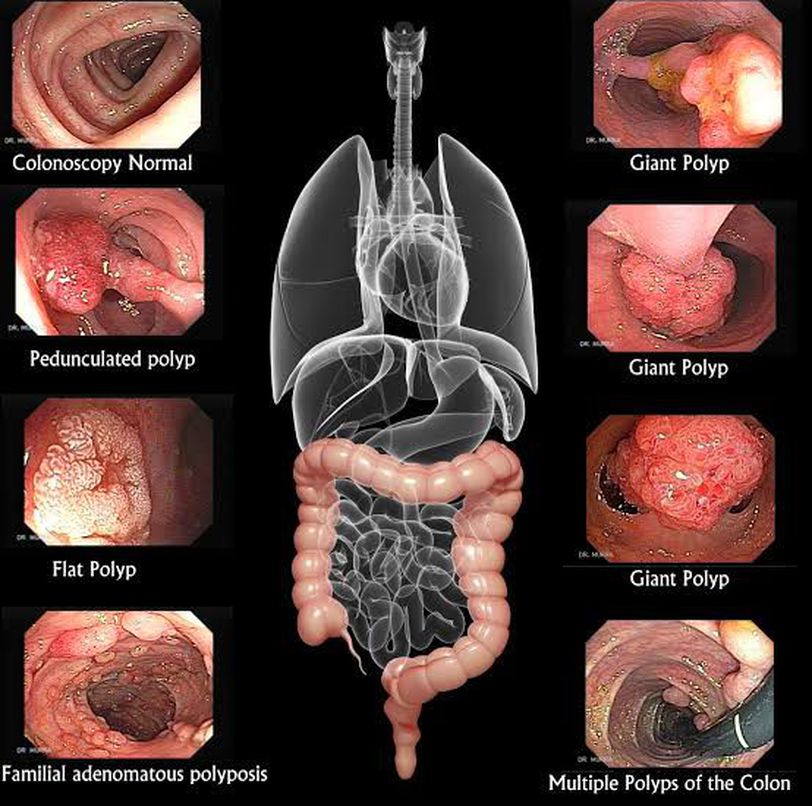

Polyps are mucosal outgrowths protruding into the organ's lumen. They are frequently encountered in the rectum and sigmoid colon. They can be of the following types: 1. Inflammatory pseudopolyps: They are formed as a result of edema of the mucosa and are usually associated with colitis. 2. Juvenile polyps: These are bright red and pedunculated, also referred to as cherry tumours. When solitary, they pose no risk of malignancy but if multiple, they might carry an increased risk of neoplastic changes. A characteristic histological feature is the presence of mucous filled spaces within the polyp. 3. Hyperplastic polyps: These polyps are small, sessile and often multiple. They do not usually carry a malignant potential. 4. Adenomatous polyps: These may be of the tubular, villous or tubulovillous variety. They have an increased risk of malignancy, especially if their size exceeds 1cm. FAP or familial adenomatous polyposis is a hereditary disorder characterized by numerous adenomatous polyps in the colon. This condition necessitates prophylactic colectomy to prevent the occurence of colonic adenocarcinoma. Ideally all polyps should be biopsied or removed to exclude cancer! Image via: http://www.gastrointestinalatlas.com/murrasaca/english/polyps.html Source: Bailey and Love's Short Practice of Surgery